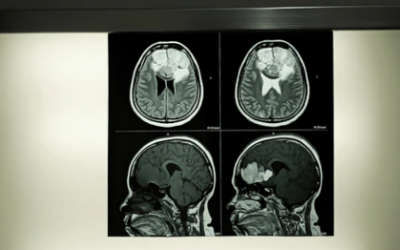

Liver Cancer

Kidney Cancer

Lung Cancer

Colon Cancer

Esophageal Cancer

Rectal Cancer

Stomach Cancer